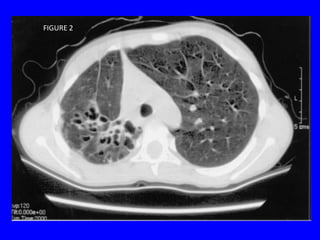

FIGURE 2

• 43.

Notes • The previousslide shows CT taken during inspiration. • Usually, a blood vessel has a bronchus beside it that has the same size. • So, if you see a bronchus larger than the accompanied vessel then suspect bronchiectasis.